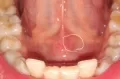

Сегодня утром появилась небольшая припухлость под языком, на уздечке языка. Никаких болевых ощущений нет. Что это может быть, и стоит ли сейчас бить тревогу?

• По фото сложно определить характер образования. Возможно, имеет место закупорка протока слюной железы. Если в течение дня ситуация будет ухудшаться, то следует обратиться к стоматологу-терапевту. Врач проведет визуальную оценку, а в случае необходимости отправит на УЗИ.